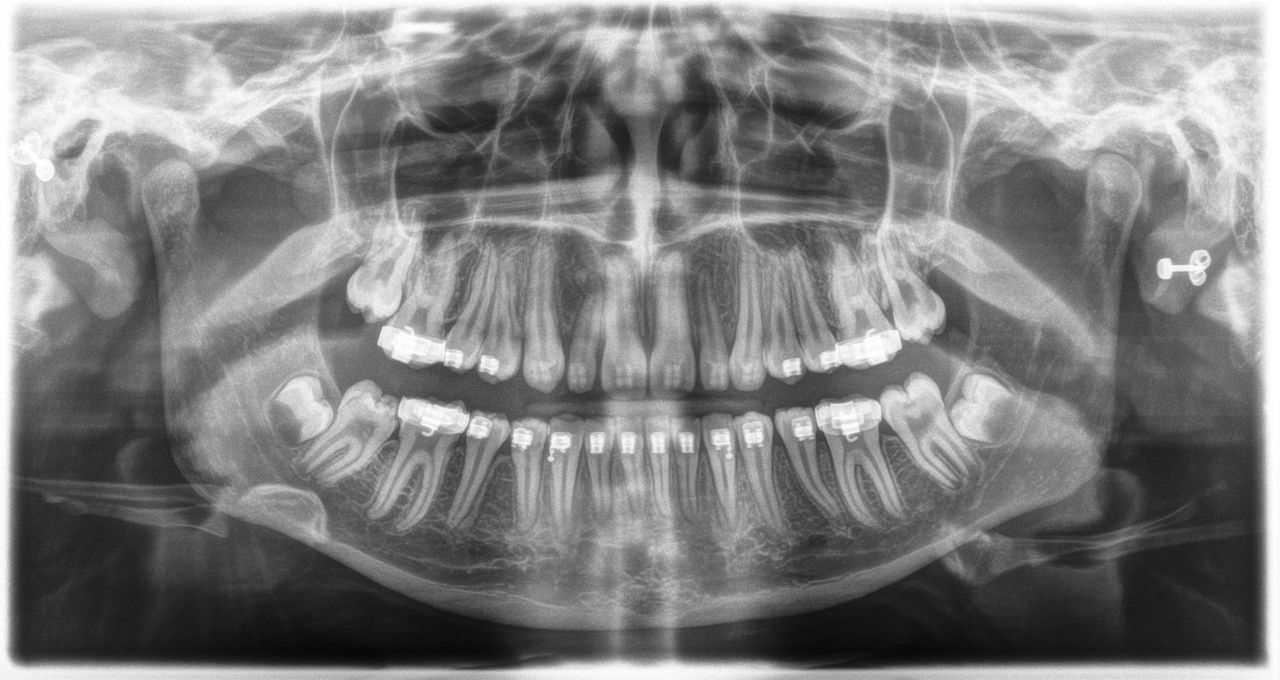

Adolescent, full dentition with orthodontic braces. Agenesis of teeth 18 and 28 with the presence of odontoblasts in 38 and 48. The incomplete root growth in 37 and 47 as well as the root development of the two wisdom teeth are evidence of the patient's young age. Maxillary sinuses and surrounding anatomical structures not radiographically apparent